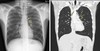

Imaging

CXR: ARDS, exclude perforated DU

Respiratory: ARDS, pleural effusion